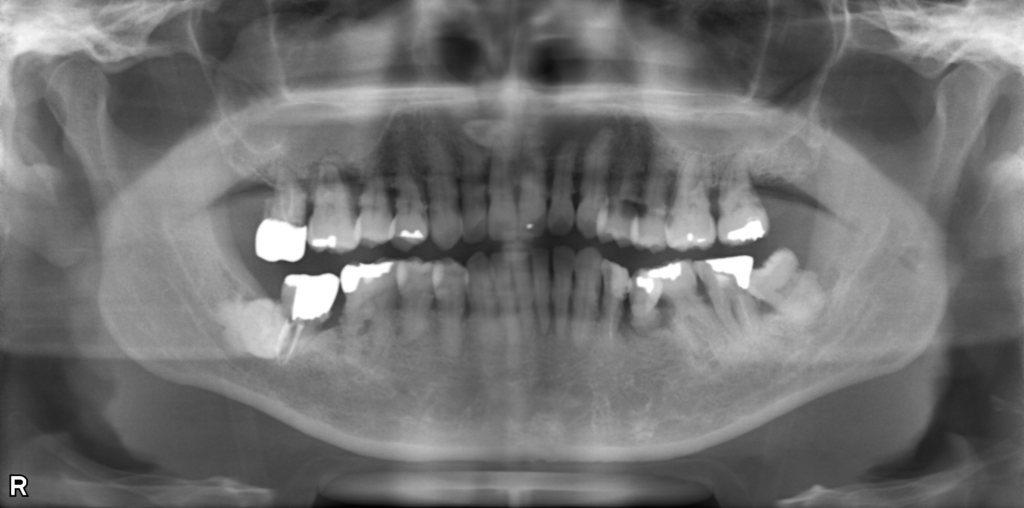

↑治療前後で骨の状態が改善しています。現在は隣の歯と固定して経過を見ています。

↑レントゲンで骨吸収を認めます。歯肉を切開すると実際に骨がありません。